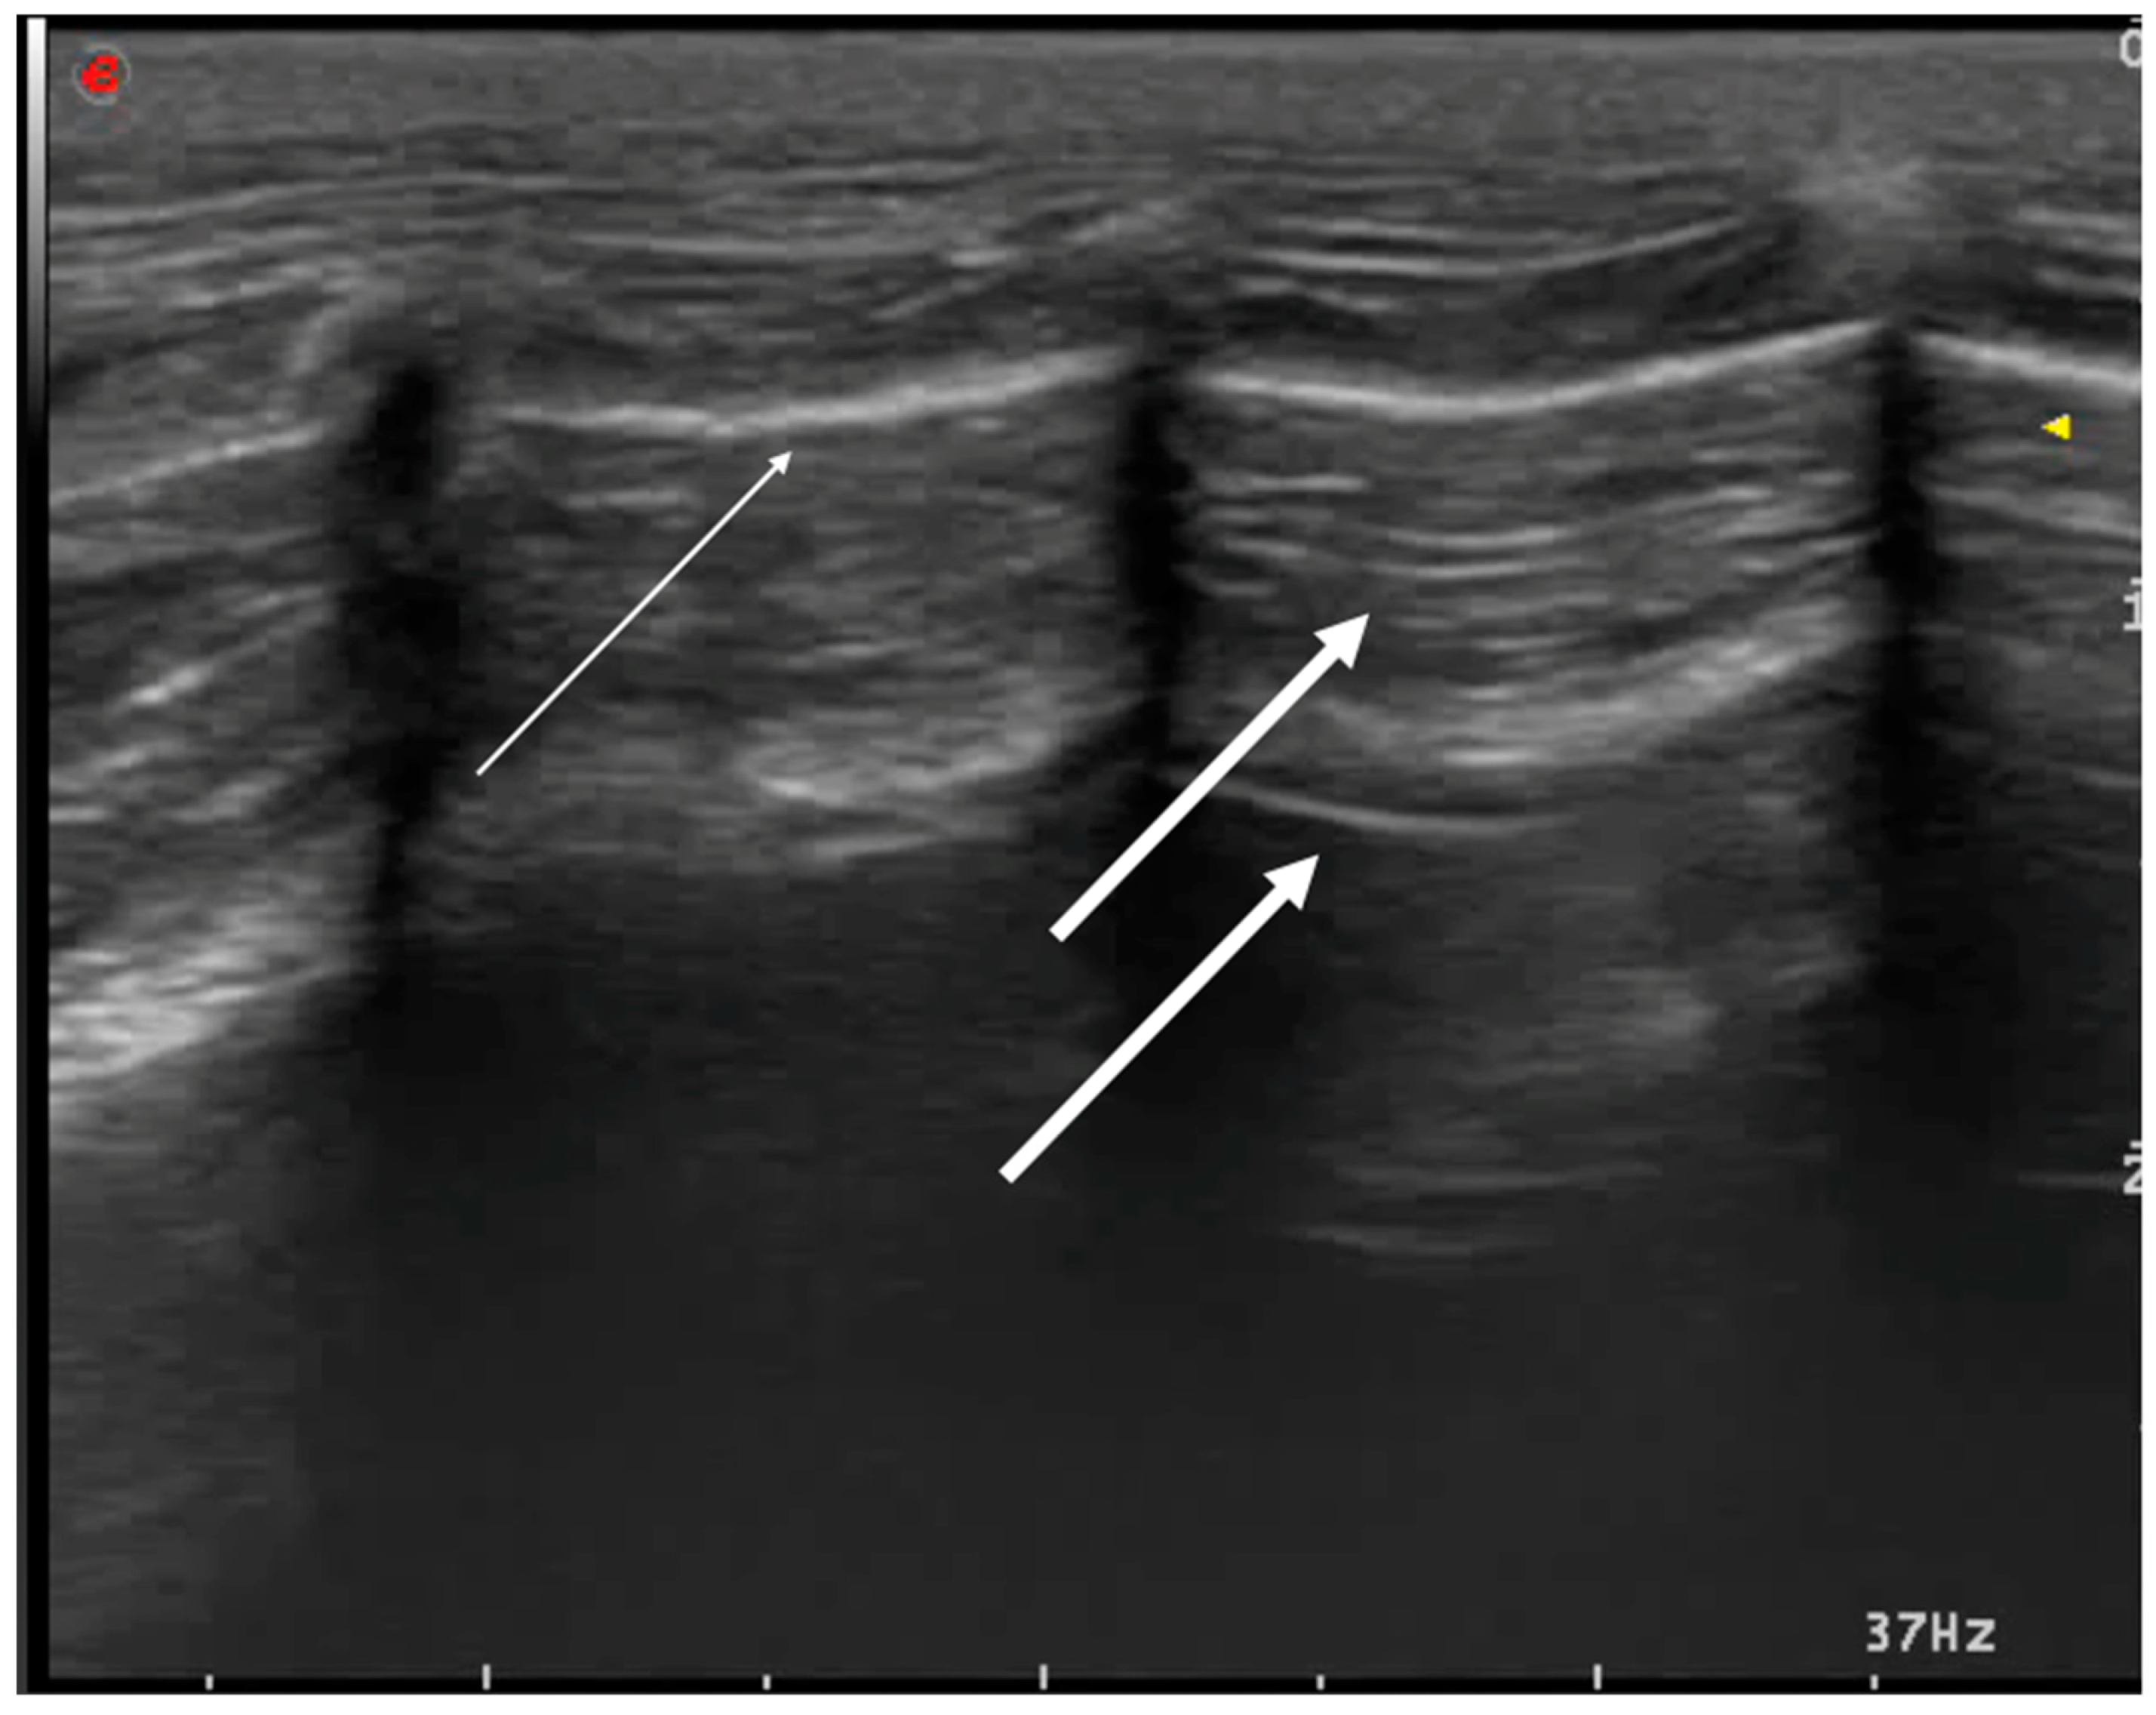

3.1.1. Pneumothorax